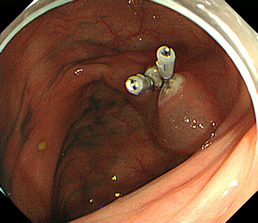

内視鏡的逆行性膵胆管造影

経口的な十二指腸内視鏡下に膵管・胆管内にカテーテルを挿入し、膵管や胆道を造影する検査です。

透視ERCP

メタルステント留置

プラスティックステント留置治療